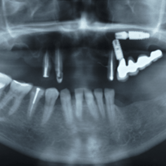

Pérdida de múltiples dientes

La pérdida de múltiples dientes es la ausencia de varios dientes que puede ser resultado de caries, enfermedades periodontales o traumatismos.

Los pacientes notan varios espacios vacíos en su boca, lo que afecta su capacidad para masticar y hablar adecuadamente.

El tratamiento incluye la colocación de varios implantes dentales para restaurar la función y la estética.